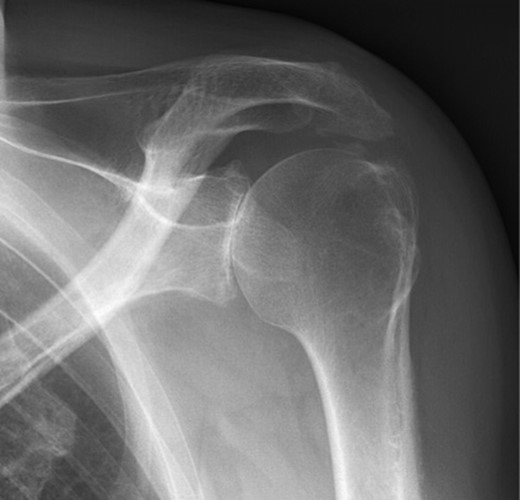

The first case is a 50-year-old man who works as a butcher. He has alkaptonuria, which was confirmed in a biopsy taken at a knee arthroscopy in 2010. He reports pain in his left shoulder. Physical examination shows an active and passively restricted range of motion. Radiological examination (Figure 1) shows glenohumeral osteoarthritis of the left shoulder. MRI shows an intact rotator cuff with signs of tendinopathy. A stemless cementless total shoulder arthroplasty was implanted (Shoulder Modular Replacement (SMR) Stemless, LIMA) (Figure 2). During surgery, the rotator cuff was intact. One year after implantation patient was satisfied regarding pain and functioning, radiography did not show any signs of loosening or other complications.

X-ray of left shoulder of patient with ochronosis. AP external rotation view showing glenohumeral osteoarthritis.